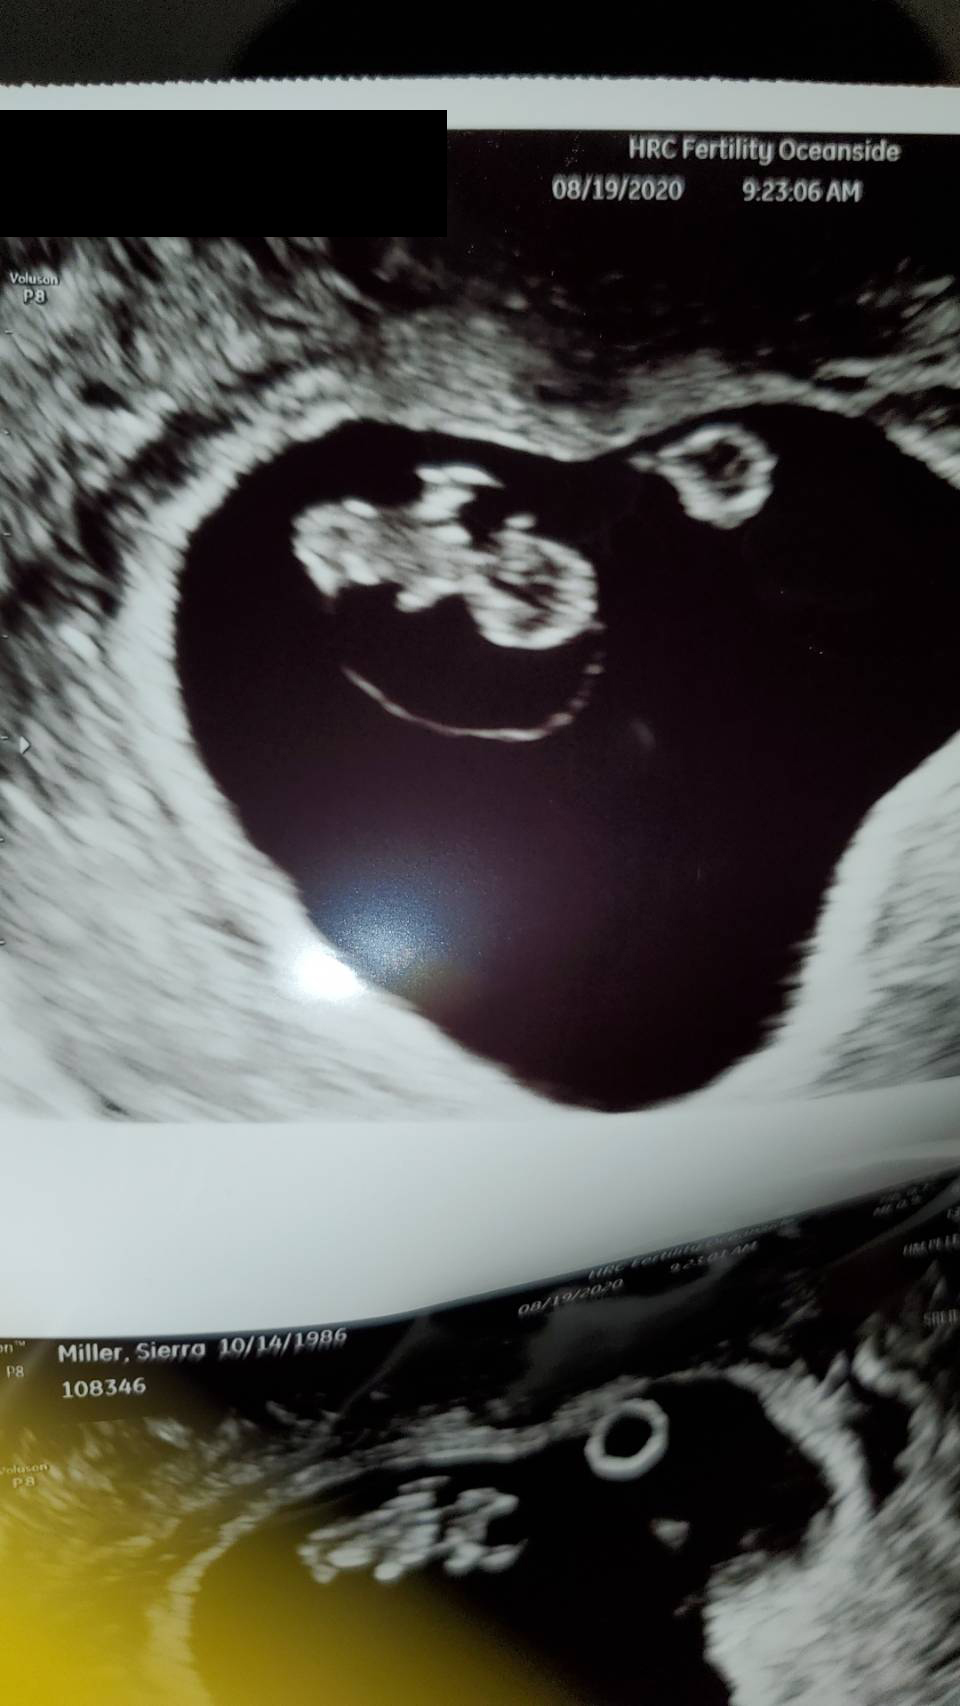

Return to Baby超音波紀錄 : 5週又5天